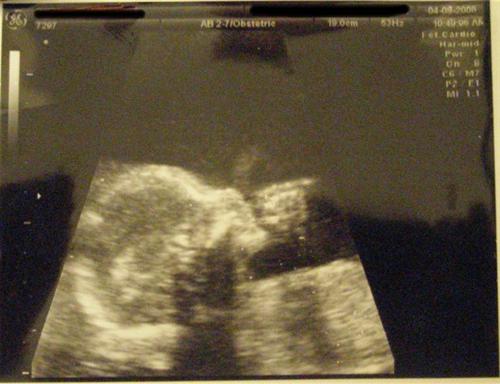

The Level 2 went well. Ed-lie Bubbles is measuring right on target. She is very healthy and moving around - tumbling and kicking - so much so that I may give her the last name "Tynes" in honor of the Giants' kicker who got them into the Superbowl. Here she is again:

Looks great!!!! You have a thumb sucker!!!